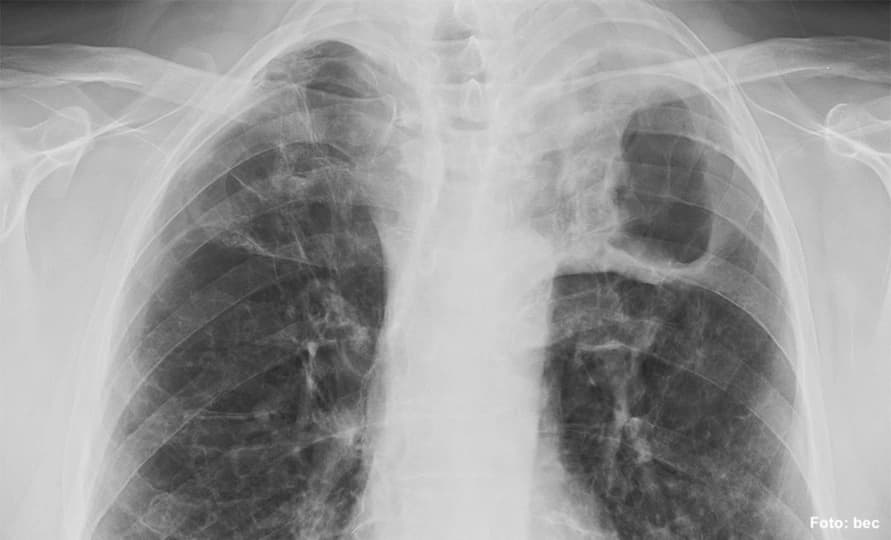

Doplňme, že tuberkulóza je v česku téměř vymýcená, každoročně se ale objevují nízké počty nakažených. Dlouhodobě však počty případů klesají. Častěji se tuberkulózou nakazí dospělí, nevyhýbá se ale ani dětem. Co se týče výskytu tuberkulózy u cizinců v Česku, ten je dlouhodobě přibližně konstantní. Podobně je na tom výskyt mezi Ukrajinci v Česku, ročně se tuberkulózou nakazí nižší desítky z nich.

V Česku je jen jedno specializované pracoviště pro děti s tuberkulózou, a to v pražské Thomayerově nemocnici. Vedoucí lékařka centra pro léčbu dětské tuberkulózy Karolína Doležalová pro iDNES.cz uvedla: „Tuberkulózu, tak jako další nemoci, které se přenášejí na člověka i ze zvířat, zcela vymýtit nelze. Před covidem jsme léčili asi 10 dětí ročně. V roce 2020 jsme kvůli pandemii i oslabení zdravotních služeb léčili jen dvě děti s tuberkulózou, ale předloni 16 a loni 17.“ 21. února bylo v Thomayerově nemocnici hospitalizováno s tuberkulózou celkem 7 dětí.